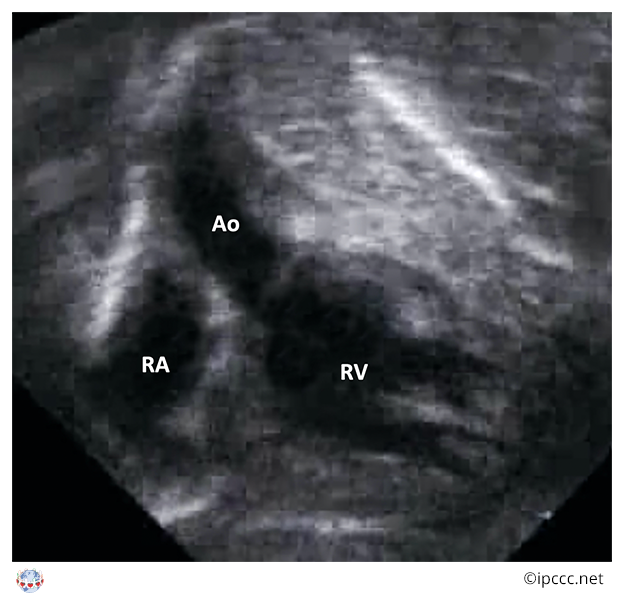

A congenital cardiovascular malformation in which the morphologically right atrium connects to the morphologically right ventricle, the morphologically left atrium connects to the morphologically left ventricle, the morphologically right ventricle connects to the aorta, the morphologically left ventricle connects to the pulmonary trunk, and a ventricular septal defect is not present.

Echocardiogram